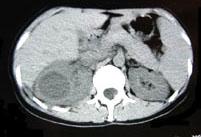

问题 女,33岁,右胁腹痛7天,尿检可见大量的脓细胞,CT平扫+增强如图所示,下列说法正确的是 ( )

选项 A、考虑为右肾囊肿合并感染 B、考虑为右肾脓肿 C、增强扫描可见该病灶不均匀强化,其内有无强化的坏死灶 D、右肾病灶边界模糊不清 E、右肾体积增大,其内可见类圆形低密度病灶

答案 BCDE